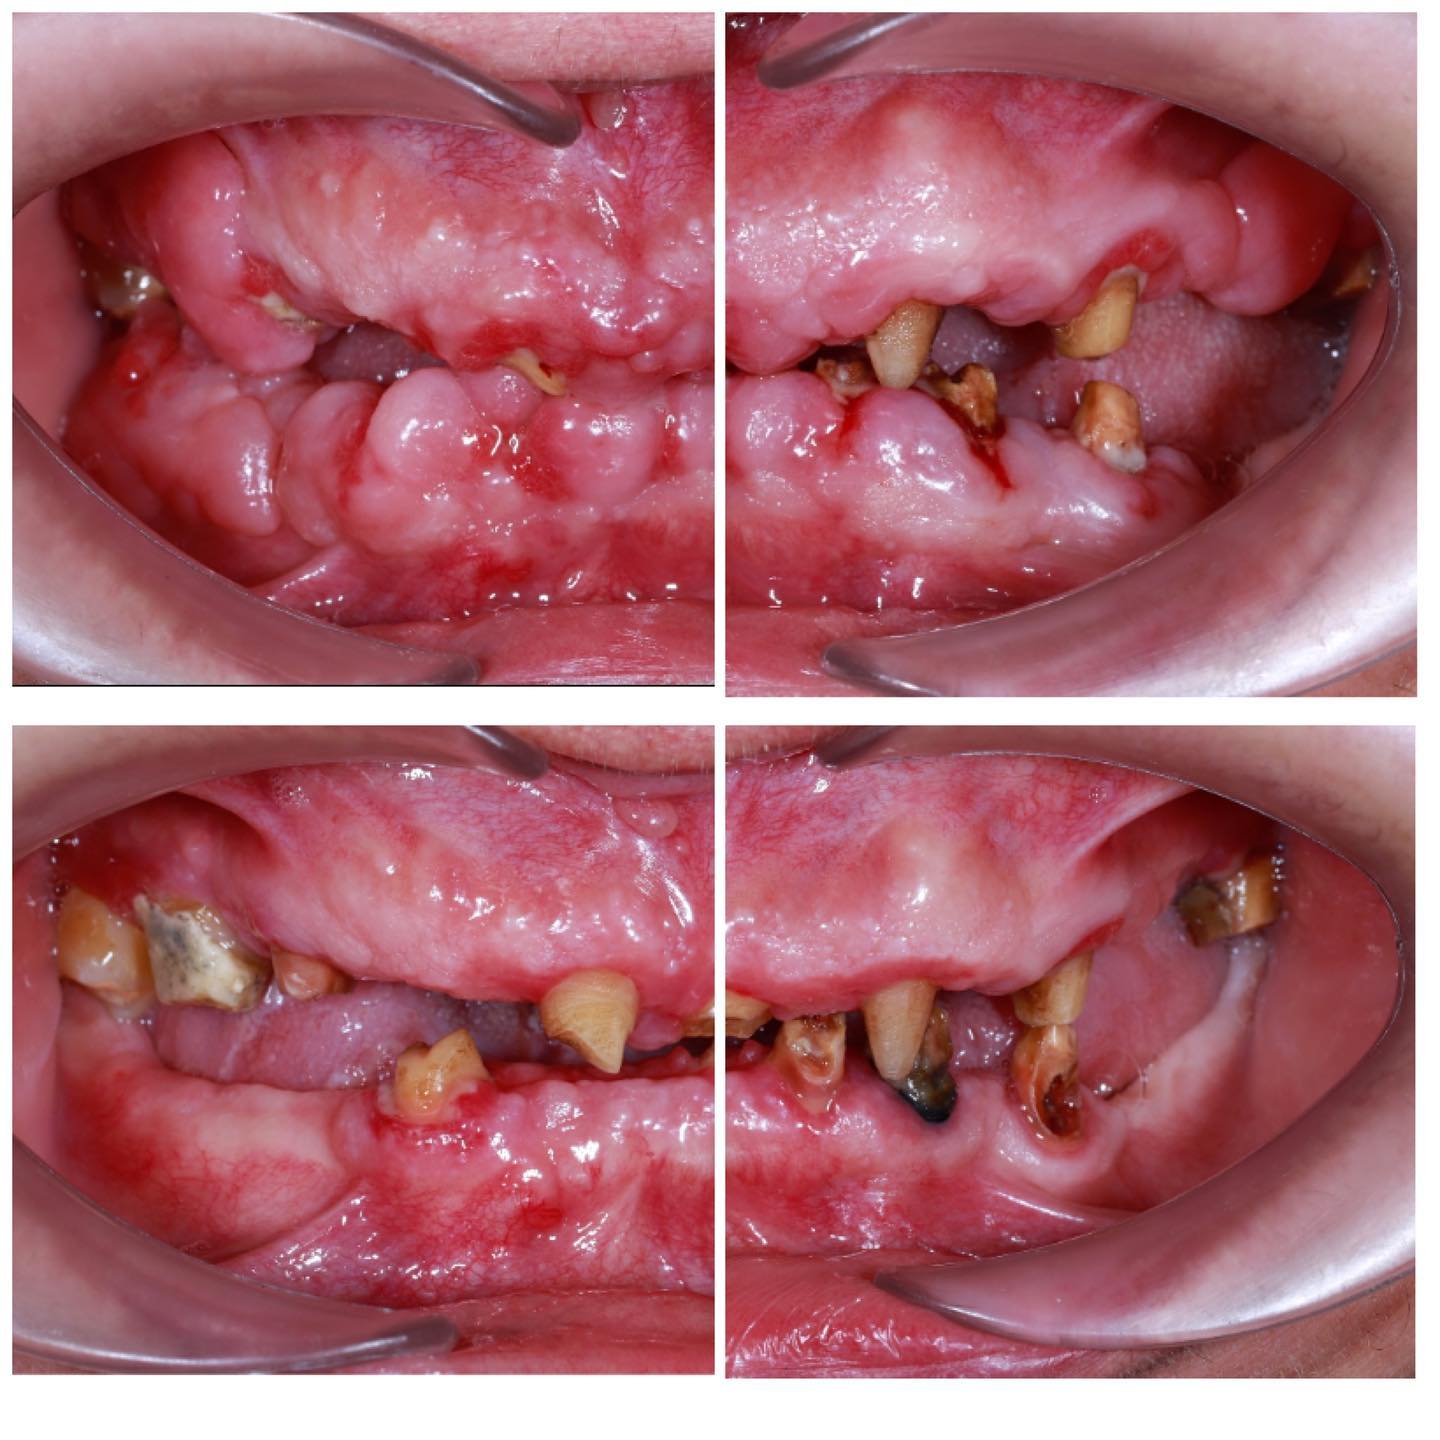

Çoxlu diş əti çəkilməsi olan xəstənin damağdan aldığımız yumuşaq toxuma ile tam qapadılması

Alt kəsici dişətinin çəkilməsi olan pasientin damaqdan diş əti parçası alaraq bərpası

Diş əti çəkilməsi olan xəstənin tunel əməliyyatı ilə çəkilmənin qapadılması